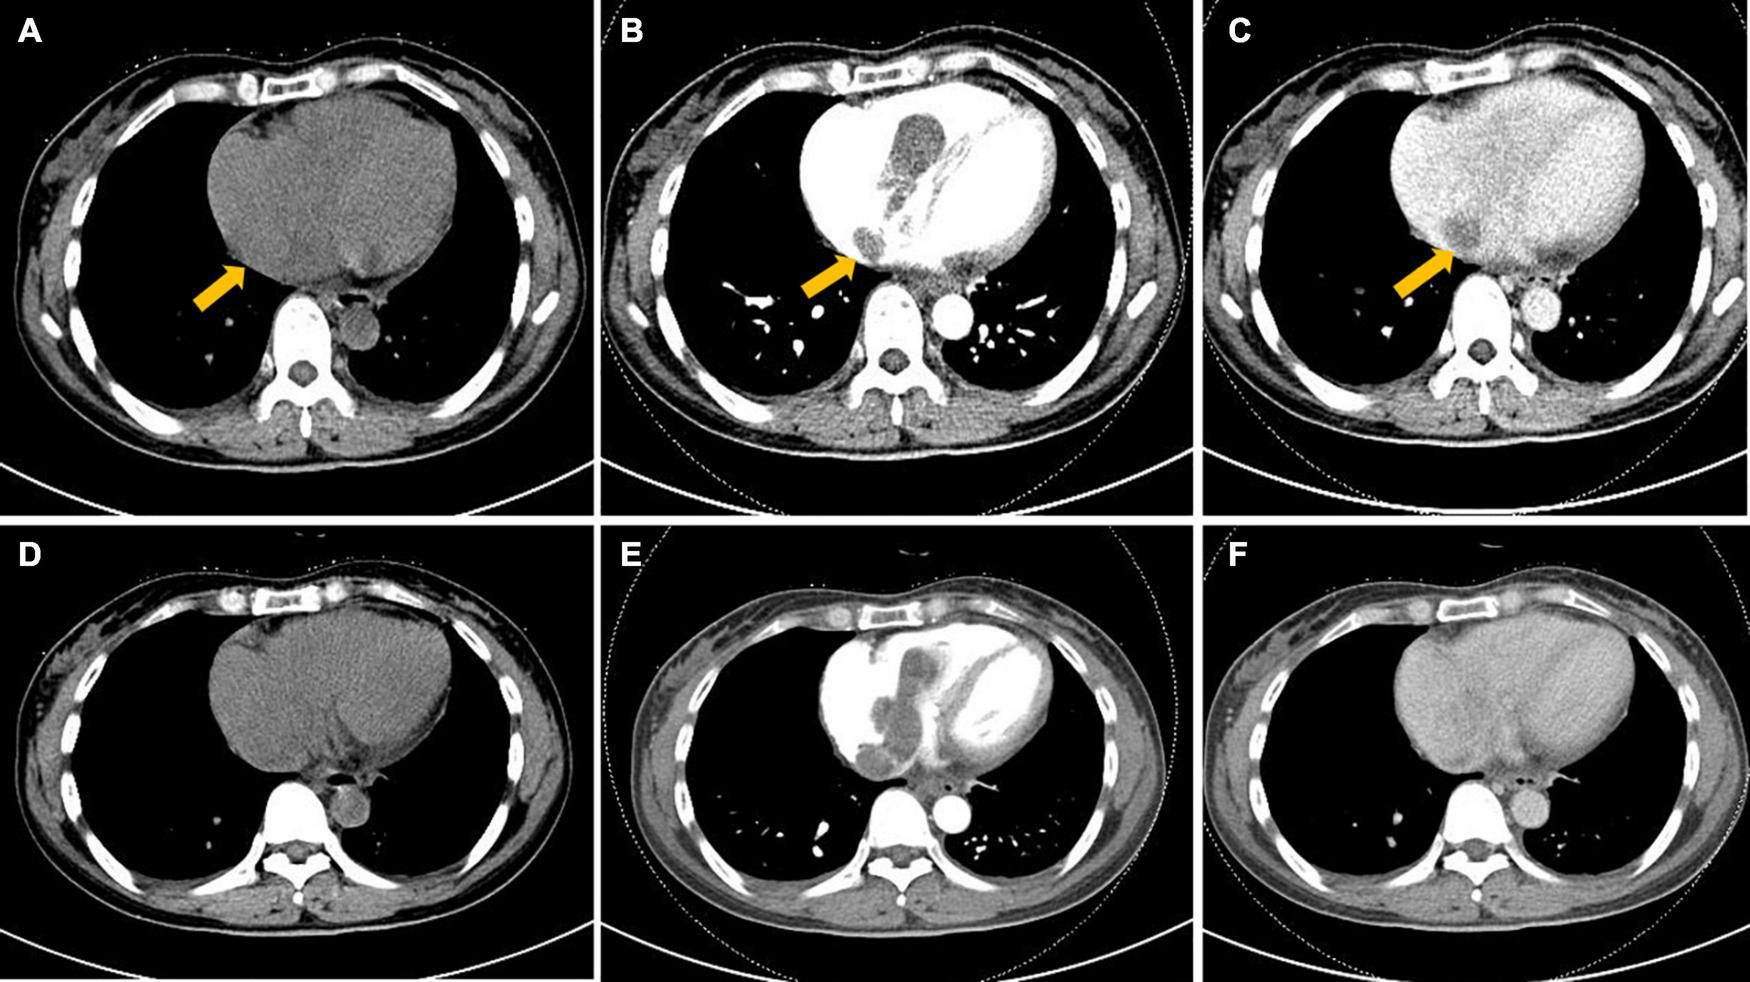

FIGURE 2

Axial computed tomography (CT) image of the heart. (A–F) Hypoattenuating filling defect located within the right atrium across the tricuspid valve into the right ventricle. Intracardiac lesions demonstrated mainly moderate progressive enhancement, with localized non-enhancing necrotic areas (arrow) on contrast-enhanced CT. (A,D) Unenhanced phase image. (B,E) Arterial phase of contrast enhancement image. (C,F) Portal phase of contrast enhancement image.